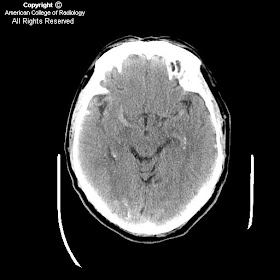

Dural arteriovenous fistula with engorgement of pial vessels and venous hypertension

Findings

Figure 1, 2, and 3: The images show engorged pial vessels.

Diagnosis: Dural arteriovenous fistula with engorgement of pial vessels and venous hypertension